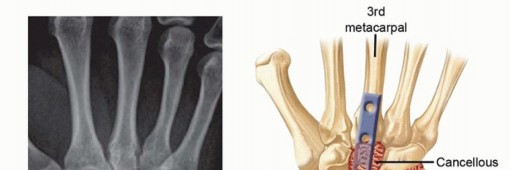

Operative Techniques in Hand, Wrist, and Elbow Sur